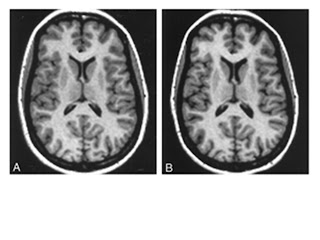

of us, because the only data I could find were structural MRI studies showing

that indeed the brain shrinks a bit, and the ventricles containing

cerebrospinal fluid get a bit bigger when you are pregnant. The 8% (that you

| Yes, this is your brain on pregnancy, from this study. A is the pre-pregnant brain, and B is the pregnant brain, at full term. Note that the ventricles are enlarged in B. (Are you also that annoyed by popular science magazines saying “this is your brain on… [insert whatever] and then show a picture of an MRI? Me too!) |

So yes, your brain gets a bit smaller when you are pregnant.